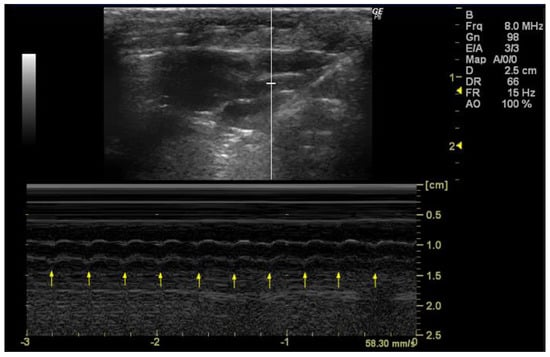

3.4.2. M-Mode

- How to measure HR